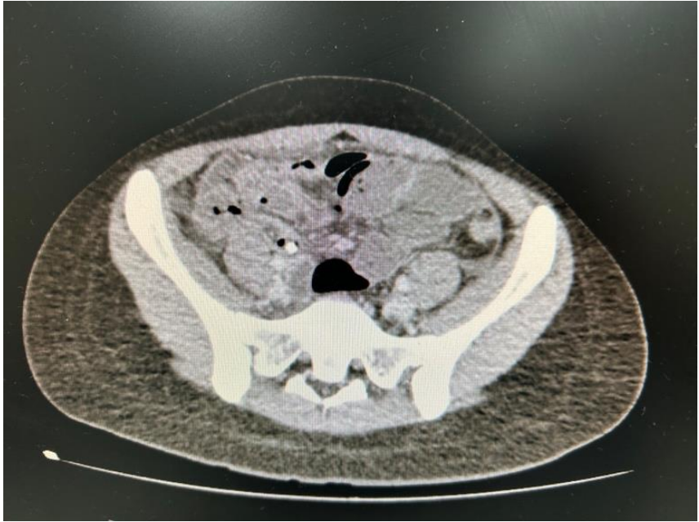

Realizou tomografia computadorizada de abdome com contraste venoso para investigação que apresentou o seguinte achado.

Dentre os diagnósticos diferenciais para esse caso, qual dos seguintes é o mais provável?